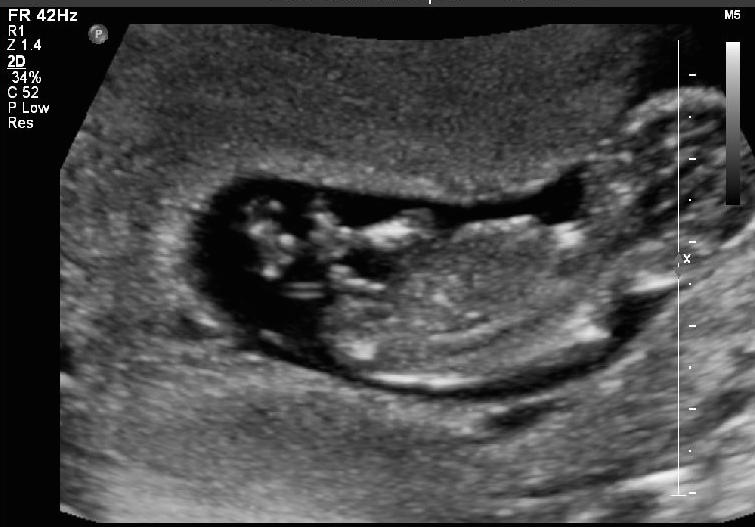

I had my anatomy scan done today. I am 12w4days. I ll get my harmony results in a day or two. Can anyone please guess?

Attachment 38073

Giving a slight boy lean. Some pics show stacking, and some show an angled nub. 🤞🏻for you!

Looks like a little boy!

Boy lean but not super confidant as baby is a bit twisted. Good luck, I hope this is your little man :happy: